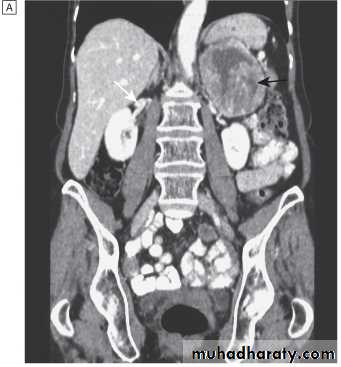

Localisation; abdominal CT or MRI.

CT scan of abdomen showing large left adrenal phaeochromocytoma. The normal right adrenal (white arrow) contrasts with the large heterogeneous phaeochromocytoma arising from the left adrenal gland (black arrows).